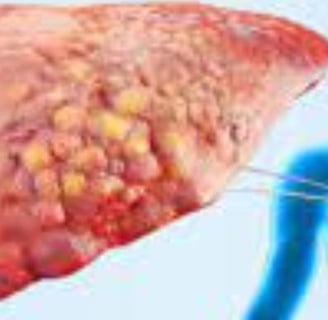

مرض الكبد الدهني، المعروف أيضًا باسم مرض الكبد الدهني غير الكحولي (NAFLD)، يتضمن تراكم الدهون الزائدة في الكبد.

يتميز مرض الكبد الدهني بوجود فائض من الدهون في الكبد، حيث تعتبر الاضطرابات الأيضية والاستهلاك المفرط للكحول من عوامل الخطر الرئيسية.

بينما قد لا يسبب تراكم الدهون مشاكل في البداية، إلا أنه يمكن أن يؤدي في النهاية إلى تلف الكبد.

مع مرور الوقت، يجعل هذا التراكم من الصعب بشكل متزايد على الكبد أن يعمل بشكل صحيح.

هناك نوعان رئيسيان من الكبد الدهني: مرض الكبد الدهني غير الكحولي (NAFLD) الذي يتضمن تراكم الدهون في الكبد، ومرض التهاب الكبد الدهني غير الكحولي (NASH) الذي يترافق مع علامات الالتهاب وتلف خلايا الكبد.

الكبد الدهني من الدرجة الأولى: يعتبر حالة خفيفة حيث تشكل الدهون 5-10% من الكبد. من المهم تناول طعام صحي وممارسة الرياضة بانتظام.

الكبد الدهني من الدرجة الثانية: يحدث عندما تتراوح نسبة الدهون في الكبد بين 10-25%.

الكبد الدهني من الدرجة الثالثة: هو الأكثر خطورة، حيث يشير إلى نسبة مرتفعة من الدهون في الكبد مع التهاب في الأنسجة المحيطة.